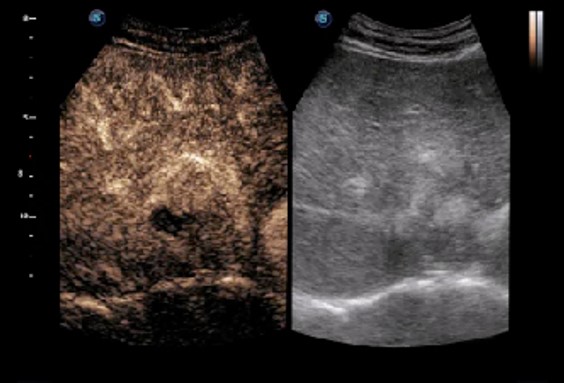

Hình ảnh tương phản

Hình ảnh tương phản với 8 đường cong TIC cho phép bác sĩ đánh giá động lực tưới máu trong một loạt các cơ sở lâm sàng, bao gồm cả vị trí và đánh giá các bộ phận tổn thương.